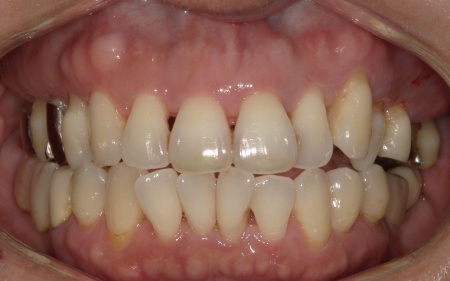

50代女性 温存が難しい奥歯を抜いてインプラントで噛み合わせを回復した症例

「他院で左上の親知らずを抜いたが、かなり腫れ、隣接する歯もグラグラするようになった。他院の説明では納得ができなかったため、セカンドオピニオンとしてこちらを受診した」とご相談いただきました。

拝見したところ、左上の抜歯部周辺は歯を支える骨が溶ける「骨吸収」が進行し、隣接している歯を含めた複数の歯がひどくグラグラしており、温存が困難です。

噛み合わせも安定していなかったため、このままでは残っている歯への負担が増加し、歯の揺れやさらなる噛み合わせの悪化につながるリスクがあります。